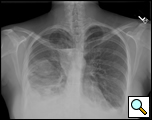

| Figure 1: Presentation chest x-ray revealing bilateral pleural effusions. |

A 35-year old woman undergoing in vitro fertilization noted progressive shortness of breath, orthopnea, and moderate right lower chest discomfort worsening with deep inspiration. She subsequently presented to her gynecologist where ultrasound evaluation revealed ascites and bilateral pleural effusions (Figure 1). She was admitted for management of ovarian hyperstimulation syndrome. A contrast chest CT scan showed massive bilateral pleural effusions, loculated on the right with a small right pneumothorax. Bilateral thoracenteses were performed with drainage of 1300cc of serosanguinous fluid on the left and minimal fluid on the right.